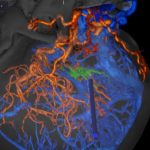

手術中

モニタリング

手術写真